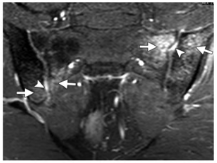

MR:可显示软骨下骨、韧带、滑膜和关节囊的软骨和急性炎症活动的初期变化,从而进行早期诊断。研究表明,MR在检测早期结构变化方面具有与CT类似的敏感性,并且对于评估脂肪沉积具有更好的灵敏度。MRI显示的骨髓水肿可为强直性脊柱炎的诊断及病情评估提供重要信息,且MRI现在正逐渐用于评估抗炎药物的疗效。

活动性炎症病变(早期改变)包括骨髓水肿,滑膜炎,关节囊炎,附着点炎。